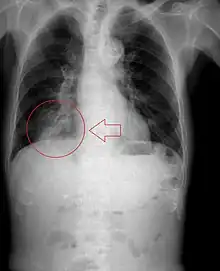

Imaging

Radiologic studies may be done to image the chest wall, lungs, and airway to evaluate and diagnose conditions that may be contributing to aspiration, and also to diagnose complications of previous aspiration.

Chest X-rays can be useful in the diagnosis of aspiration pneumonia but may be negative early in the course.[12] Chest CT Scan can identify the presence of a pneumonia as well, and can also assist in characterizing abscesses, foreign objects, or pleural disease.

A fluoroscopic swallow study can be done in cases where dysphagia or motility disorders are thought to be the source of aspiration. Food and drink are mixed with barium contrast and monitored using x-ray to evaluate swallowing. Aspiration can be diagnosed if contrast is seen coursing below the vocal cords into the trachea.[13]